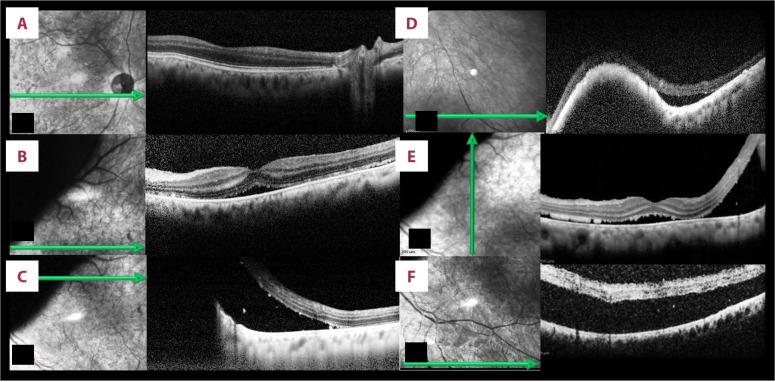

BACKGROUND Choroidal melanoma is the most common primary intraocular tumor in adults. Most primary choroidal melanomas are unilateral and unifocal. Bilateral primary choroidal melanomas are considered to be a rare occurrence. Ocular melanocytosis, especially when it is bilateral, increases the incidence of bilateral primary choroidal melanoma. CASE REPORT Our patient was a 78-year-old man who presented to the Emergency Department with floaters and a reduction in visual acuity in his left eye, with an onset 7 days prior. Upon macroscopic examination, the patient displayed bilateral pigmentation on the sclera, which was consistent with ocular melanocytosis. Fundoscopy revealed a large choroidal melanoma, situated superior and nasally of the posterior pole of the left eye, and a smaller choroidal melanoma, located inferonasally, in the right eye. Ultrasonography, optical coherence tomography, fundus autofluorescence, fundus fluorescein, and indocyanine green angiographies were performed, confirming the diagnosis of simultaneous bilateral primary choroidal melanomas. CONCLUSIONS This was a rare case of bilateral ocular melanocytosis, which increased the probability of bilateral primary choroidal melanoma. To the best of our knowledge, this is the first case in Greece to be reported. This case illustrates the necessity of always examining the fellow eye on initial presentation and over a long follow-up. We should always bear in mind that choroidal melanoma can be a bilateral disease, albeit very rarely.

我们的患者是一名 78 岁男性,因左眼出现漂浮物和视力下降而到急诊科就诊,发病时间为 7 天前。宏观检查显示,患者的巩膜双侧均有色素沉着,符合眼黑色素细胞增多症的表现。眼底检查显示左眼后极上方和鼻侧有一个大的脉络膜黑色素瘤,右眼鼻下方有一个较小的脉络膜黑色素瘤。进行了超声检查、光学相干断层扫描、眼底自发荧光、眼底荧光素血管造影和吲哚青绿血管造影,确诊为双侧同时性原发性脉络膜黑色素瘤。